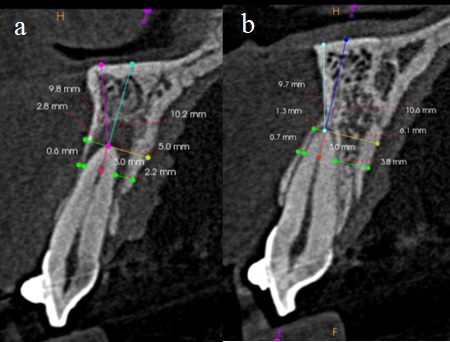

Notas: a) Diente con indicación de microcirugía apical; b) diente sin indicación de microcirugía apical